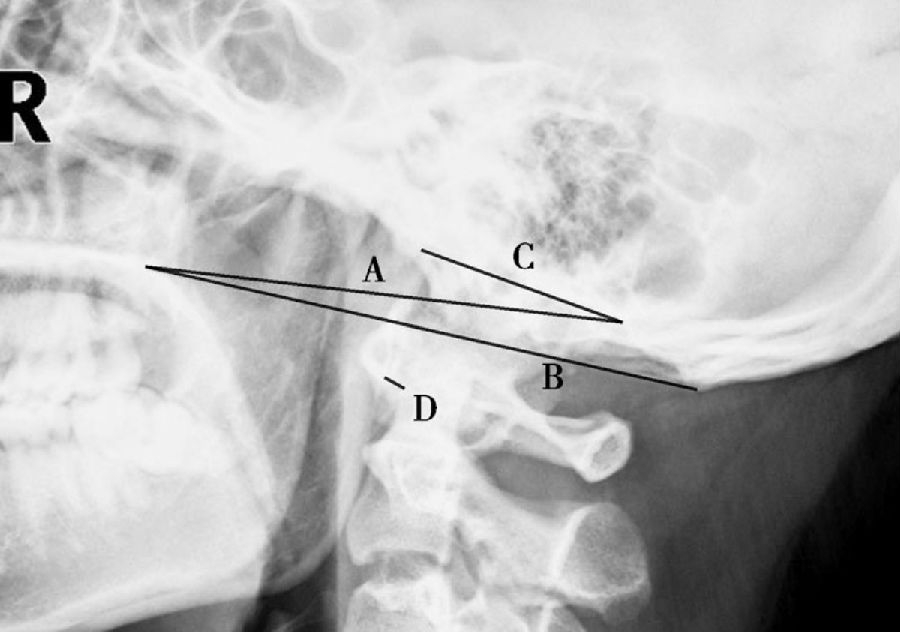

图5 颅颈交界侧位片测量图

A. Chamberlain线(腭枕线),硬腭后上缘至枕大孔后唇连线;B. McGregor线(基底线),硬腭后上缘至枕骨最低点(枕骨鳞部外板最下缘)连线;C. Mc Rae线,枕骨大孔前后缘连线;D. 寰齿前间隙。颅底凹陷:齿突尖部分别超出A、B、C线5mm、7mm及0mm。

(1)Chamberlain线(腭枕线):颅颈交界侧位片,硬腭后上缘至枕大孔后唇连线,齿突尖端若超过此线上方5mm,提示颅底凹陷(图5、图7)。

(2)McGregor线(基底线):颅颈交界侧位片,硬腭后上缘至枕骨最低点(枕骨鳞部外板最下缘)连线,齿突尖端若超过此线上方7mm,提示颅底凹陷(图5)。

(3)Mc Rae线:颅颈交界侧位片,枕骨大孔前后缘连线,齿突尖端若超过此线提示颅底凹陷(图5)。

(4)寰齿前间隙:颅颈交界侧位片,寰椎前弓与枢椎齿突前缘的距离。正常值:女性1.238mm(0.007 4×年龄)±0.90mm;男性:2.052mm(0.019 2×年龄)±1.00mm;3~10岁儿童:2.8mm±0.50mm。成人此间隙大于3mm,儿童大于5mm,提示寰枢关节半脱位(图5、图6)。